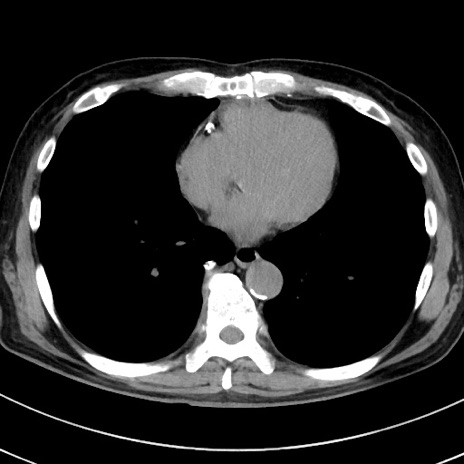

症例38(横断像)

【症例】70歳代 男性

【主訴】腹痛・嘔吐

【現病歴】昨晩より、嘔吐・腹痛あり。今朝になっても嘔吐あり。来院。

【既往歴】心臓バイパス手術、開腹胆摘、腸閉塞

【身体所見】BP 107/71mmHg、HR 116/min、腹部:平坦、軟、下腹部に軽度圧痛あり。反跳痛なし。

【データ】WBC 15100、CRP 0.32